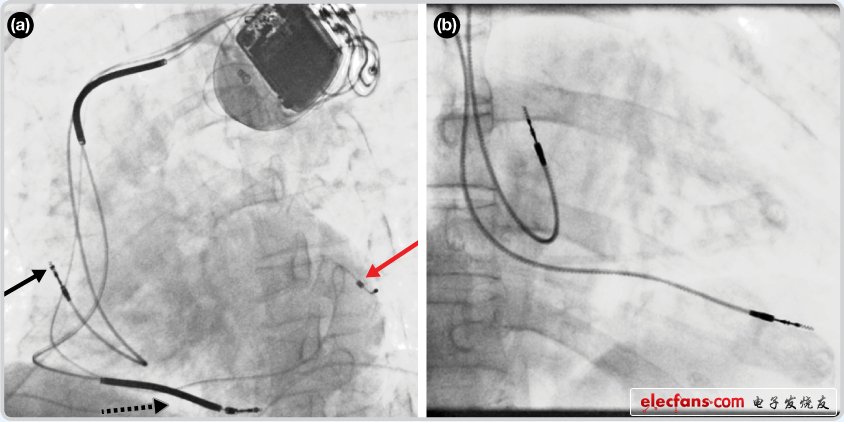

1354 研究人員表示,這是首次實現(xiàn)利用消融導管結合近紅外光譜學映射,成功區(qū)分心捐贈與心血管疾病患者各種組織的類型。目前,大多數(shù)臨床心臟測繪系統(tǒng)都是基于功能測量,如能將提供底層組織組成信息的光學測量與標準功能方法共同使用,可以顯著提高消融成功率。